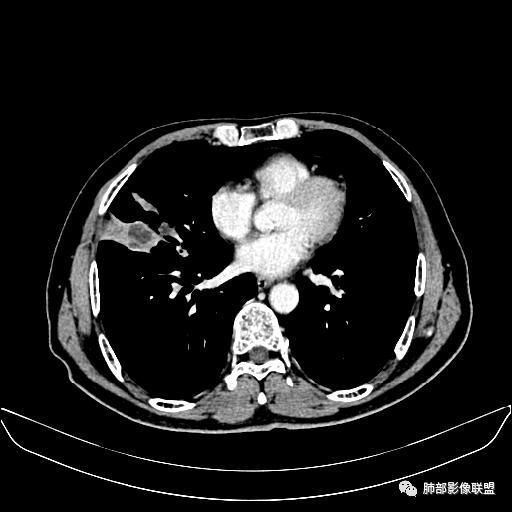

住院4天后行胸部增强CT

静脉期

老年男性,因“咳嗽咳痰1月余。”入院。病程中咳嗽咳痰,咳黄白痰,间断咯少许鲜红色痰血。PPD阳性。胸CT:右肺中叶外侧段支气管管腔阻塞,大片实性病变,病灶边缘光滑,部分边缘膨隆,可见分叶,肺门及纵隔可见肿大淋巴结,并可见钙化。增强可见病灶明显强化,而且延迟强化明显,病灶内多发低密度区,内见血管影,血管变细、部分血管破坏。考虑恶性病变可能性大,鉴别慢性肉芽肿性病变。

胸CT:跨叶大肿块,主体在中叶,右中叶外侧段支气管阻塞,病灶部分边缘膨隆,可见分叶,部分边缘平直,肺门及纵隔可见肿大淋巴结。增强病灶不均匀强化,延迟强化明显,病灶内多发低密度区,内见血管飘浮,部分血管变细、模糊。考虑:恶性病变可能性大,大细胞?淋巴瘤?鉴别慢性肉芽肿性病变。

右肺中叶软组织肿块,外围向内生长,叶间胸膜向前内移位,肿块近肺门侧跨叶,中叶外侧段支气管截断,密度不均匀,双侧肺门及隆突下见肿大淋巴结,增强后呈中度不均质强化,肺动脉供血,多发坏死区,边界尚清,坏死区域内见结构,结合病史考虑恶性,鉴别诊断1结核,爬行征是沿支气管树分布,外宽,内窄,周围有卫星灶,内气管狭窄后扩张,此例沿叶间胸膜长轴分布,气管有截断,不典型。2炎性肉芽肿,符合的地方下方层面增强后延迟性轻度环形强化,不符临床无发热等急性感染病史,实验室指标不符,病灶周围渗出及慢性炎性改变有,不明显。

吴婧老师和南边老师都对该病例进行了深入分析。从支气管管壁的增厚,支气管狭窄后扩张,支气管粘液栓,病灶形态,到病灶不均匀强化及坏死彻底,到周边病灶及肺组织空气的潴留,加之纵隔内淋巴结肿大伴钙化等等,都支持慢性炎性病灶,尤其是结核。

墨西哥仙人掌征---结核        影像上结核灶,粗大的均匀枝干,推测是支气管囊状扩张引起的,在非支气管区,形成圆形坏死囊群;如果这些坏死比较稀薄,又遇到扩张支气管,就会形成粗大的“墨西哥仙人掌”。结核引起的支气管近端炎症纤维化,可以造成支气管阻塞,从而将干酪样坏死物封堵在管腔内。仙人掌主干内部应该是干酪为主,稀薄的,具有流动性,时间久了会出现钙化。

结核坏死与鳞癌鉴别有一点是结核坏死没有方向性,鳞癌有。鳞癌靠近支气管近端部分,血供容易维持,不易坏死,所以坏死靠外侧。而结核干酪样坏死,把一定体积的流动性坏死物,包裹起来,什么形状最省料?坏死物包裹,表面积最省的自然是圆球形,而遇到支气管,坏死物一多,就把支气管撑大了。包裹物是就地取材,扩张的支气管就成了包裹结构。